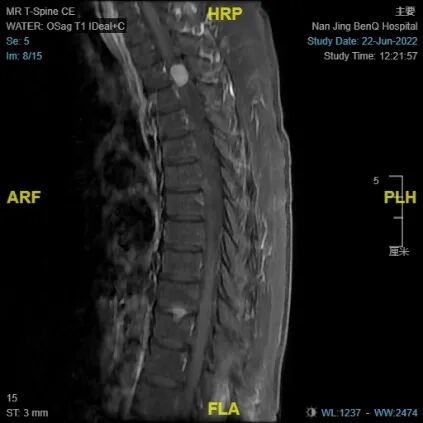

术前MRI

于是,朱阿婆去当地医院进行检查,胸椎MRI检查的结果提示 胸2-3椎管内异常信号,考虑脊膜瘤或者神经鞘瘤。经多方打听和深思熟虑之后,最终朱阿婆选择了南京医科大学附属明基医院副院长、神经外科王汉东教授团队进行治疗。在入院之后,王汉东教授发现:朱阿婆的胸部椎管占位情况严重,肿物的体积约为:1.51*1.08*0.89cm,紧紧地压迫脊髓,造成了严重的神经压迫症状。这也是朱阿婆下肢乏力,大小便异常的原因所在。